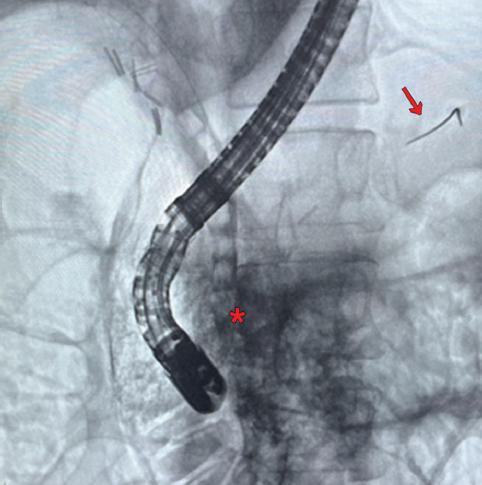

Mujer de 55 años de edad con antecedente de diabetes mellitus y dislipidemia, colecistectomía 2 años antes. Enviada por hallazgo incidental de coledocolitiasis múltiple en ultrasonido abdominal confirmada con colangioresonancia magnética evidenciando dilatación de via biliar extrahepática de 14 mm y 6 litros de hasta 9 mm en colédoco. Ingresa a procedimiento de CPRE bajo intubación orotraqueal iniciando canulación con esfinterotomo y guia 0.035” teniendo más de 3 accesos al conducto pancreático ocurriendo migración de porción hidrofílica distal de guía 0. 035” al conducto pancreático dorsal. Se logró acceso al conducto biliar evidenciando en la colangiografía dilatación de la vía biliar extrahepática y múltiples litos en colédoco. Se realizó esfinterotomía sin eventualidad aparente y posteriormente barridos con balón biliar extrayendo 6 litos. Durante el procedimiento ocurrió desaturación hasta 20% a pesar de manejo avanzado de la vía aérea por lo que fue reintubada tras múltiples intentos reiniciando CPRE canulando conducto pancreático y logrando extracción de cuerpo extraño (porción hidrofílica de guía 0.035”) en región distal de páncreas con ayuda de canastilla biliar colocando prótesis pancreática de 7 french x 5 cm. Al término del procedimiento se apreció enfisema subcutáneo masivo que afectaba región periorbitaria, cuello, tórax, abdomen y región proximal de miembros pélvicos. Se introdujo gastroscopio no apreciando perforación de duodeno. En control fluoroscópico se evidenció fuga de material de contraste a retroperitoneo sugestivo de perforación tipo 2 de Stapfer (Fig. 1) Ante la presencia de enfisema masivo y reintubación dificil se sospecha lesión traqueal. Se realizó tomografía contrastada de cuello, tórax y abdomen identificando enfisema subcutáneo con compromiso facial, orbitario, cuello, tórax, abdomen, miembros pélvicos, así como neumotórax, neumomediastino y neumoperitoneo. Se evaluó por el servicio de cirugía de cabeza y cuello sin evidenciar disrupción traqueal ni lesión en vía aérea (Fig. 2). Se ingresó a unidad de cuidados intensivos colocando sondas endopleurales de forma bilateral. Fue documentada elevación de amilasa y lipasa mayor a 1500 UI/L catalogándose como pancreatitis post CPRE. Ante inestabilidad hemodinámica con necesidad de escalar apoyo aminérgico sin respuesta se realizó laparotomía exploradora encontrando hematoma retroperitoneal no expansivo de 10 x 10 cm. No se identificó sitio de perforación duodenal. Se colocó penrose en cara posterior del duodeno, obteniendo 50 cc de líquido peritoneal con análisis del citoquímico y citológico cumpliendo criterios para peritonitis bacteriana secundaria. Paciente cursa con evolución tórpida con sepsis abdominal y falla multiorgánica falleciendo 48 horas posteriores a la CPRE.

En el caso de la paciente, se consideró se trató de una perforación post CPRE tipo 2 de Stapfer asociada con la esfinterotomía biliar y la manipulación ampular para acceder al conducto pancreático10. El mecanismo propuesto por el cual una perforación periampular puede condicionar enfisema masivo es el siguiente: posterior a la perforación periampular, el aire insuflado se extiende al espacio pararrenal derecho, hiato diafragmático, mediastino respectivamente, causando neumomediastino y neumotórax11,12, y si la insuflación continua causa enfisema cervicofacial, parafaríngeo, retrofaríngeo, e incluso orbitario5. Un dato relevante a tener en cuenta es que el tamaño del enfisema no es proporcional al tamaño de la perforación11.